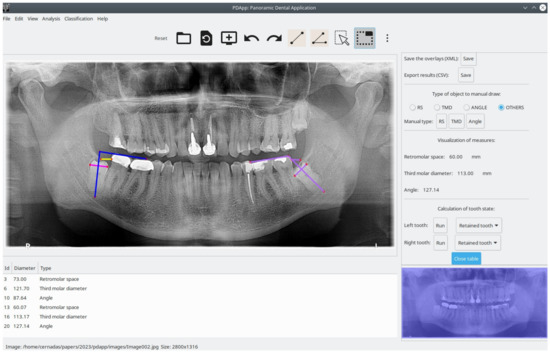

Panoramic Dental Application (PDApp) is a desktop tool that runs on a general-purpose computer under the Linux and Windows operating systems. It was written in the C++ programming language using the GIMP Tool Kit (GTK+) library (https://www.gtk.org/ (accessed on 16 February 2023)) to develop the GUI. Figure 1 shows the GUI of PDApp with a typical radiological image loaded, processed, and reviewed by a dental expert and with the lateral panel displayed.

Figure 1. Screenshot of PDApp v.1 software with analysis of typical panoramic radiograph and lateral panel open. In the right molar, the pink line represents third molar diameter, the yellow line represents retromolar space, and blue lines represent the angle. Measurement of the left molar (violet objects) are shown in the lateral panel.